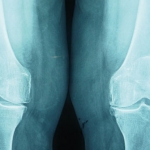

RX de rodillas artrosicas, propuestas para PTR. De momento controladas con tratamiento